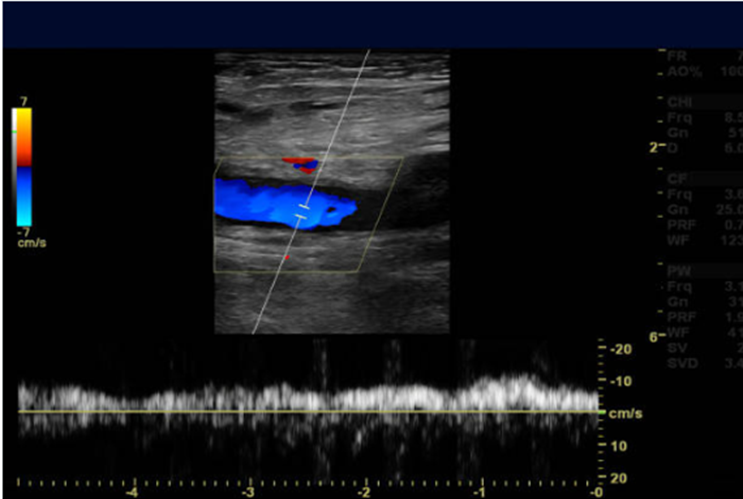

Deep Vein Thrombosis (DVT) 20 minutes

Whole body ultrasounds provide a non-invasive, painless, imaging option, allowing for the assessment of various organs without exposure to radiation.

This screening can help identify abnormalities such as tumors, cysts, or vascular issues at an early stage, potentially improving treatment outcomes. Our general screening exams include: breast, thyroid, kidneys, liver, spleen, aorta, pancreas, and calf veins.